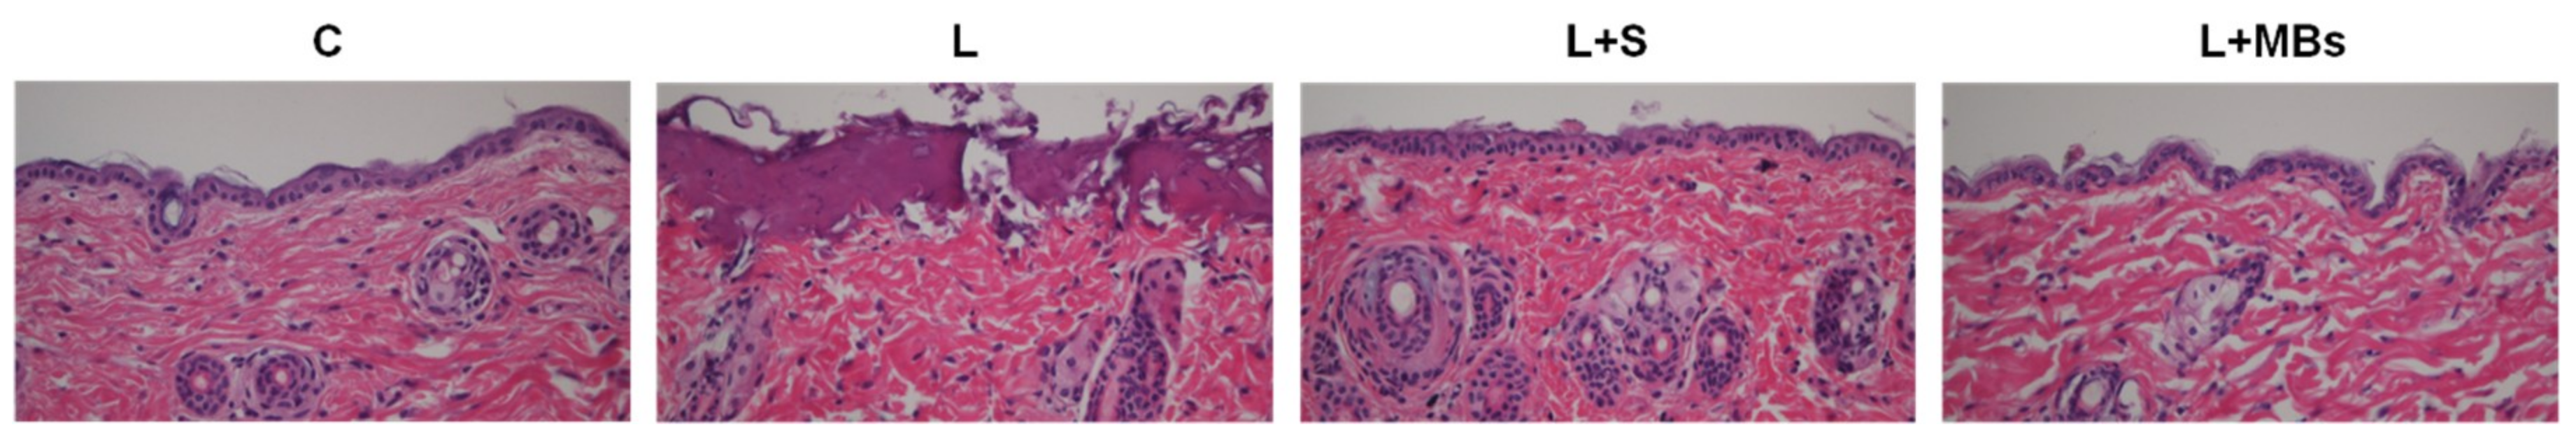

Figure 6 shows that when using the clinical CO2 fractional pulsed laser, the degree of penetration in both the cuticle and the dermis was significantly greater for tenfold-diluted MBs group (22.38 ± 3.35 μm) and laser direct irradiation (23.82 ± 3.26 μm) than for the other groups, and did not differ significantly between the saline group with laser irradiation (16.00 ± 1.33 μm) and the control group (16.19 ± 2.71 μm). However, Figure 7 shows that damage to both the cuticle and the dermis was more obvious for direct laser irradiation in HE-stained microscopy images.

Figure 7.

Light-microscope hematoxylin and eosin (HE) evaluation of pigskin samples in group C, for irradiation with the CO2 fractional pulsed laser directly (group L), and for laser irradiation combined with saline (group L + S) and tenfold-diluted MBs (group L + MBs).

Figure 3 and Figure 4 show that significant disruption occurred for the tenfold-diluted MBs after either 180 s of pulsed-laser irradiation or seven applications of CO2 fractional pulsed-laser irradiation and without any significant increase in temperature, indicating that inertial cavitation was produced effectively under these conditions. Consistently, Figure 5 and Figure 6 indicated that the penetration depth of Evans blue was greater for the tenfold-diluted MBs groups than for the other groups, and was proportional to the degree of MB rupture. These results indicate that the laser-induced inertial cavitation of MBs could also play an important role in TDD. Figure 6 and Figure 7 show that although the penetration depth of Evans blue in group L was similar to that in group L + MBs, some damage did occur in the stratum corneum. MBs might therefore also act as a buffer for reducing damage during laser irradiation.